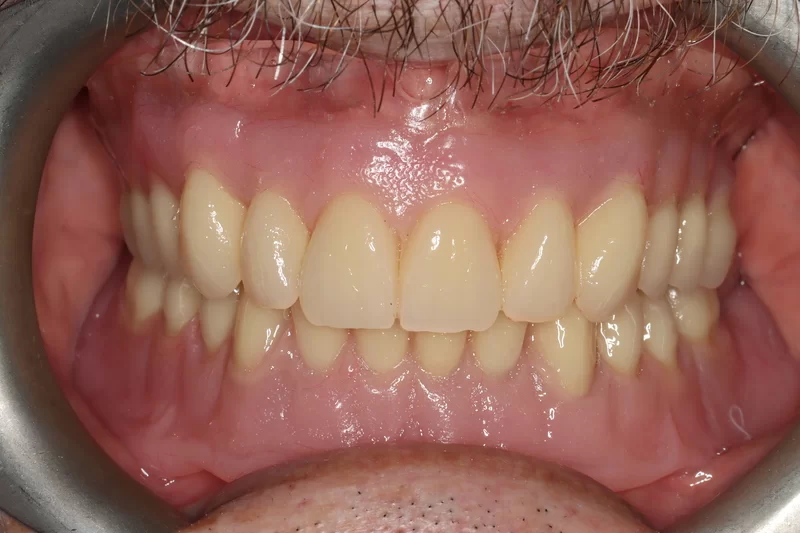

Case 37 – Implants

Upper complete denture and lower implant retained complete denture